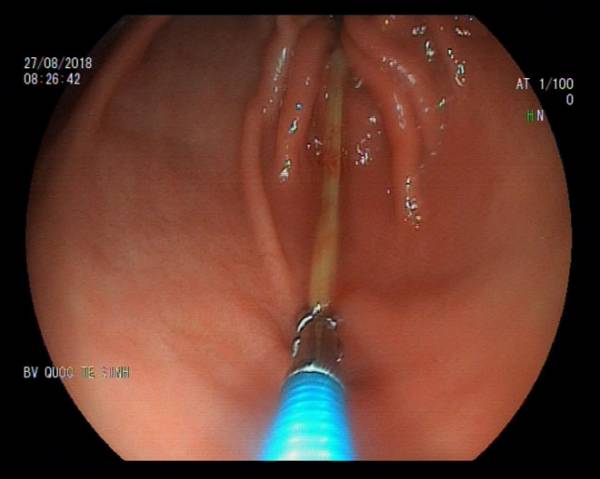

Bệnh viện quốc tế Vinh (Nghệ An) cho biết vừa phẫu thuật nội soi, gắp thành công que tăm dài 7 cm trong bụng anh Nguyễn Văn Th. (40 tuổi, trú xã Nghi Hải, thị xã Cửa Lò, Nghê An) ra ngoài.

Tại đây, qua thăm khám và tiến hành nội soi, các bác sĩ phát hiện có 1 dị vật trong dạ dày của bệnh nhân T. Bác sĩ bệnh viện sau đó nội soi để lấy dị vật ra ngoài. Dị vật đó là 1 cái tăm nhọn dài 7cm.

Theo Bác sĩ Phùng Thị Hằng, Trưởng khoa Nội (Bệnh viện Quốc tế Vinh, là người trực tiếp tiến hành lấy dị vật ra) cho hay, chiếc tăm nằm ở mặt sau hành tá tràng, một đầu nhọn cắm vào thành ruột gây chảy máu.

Di vật là que tăm dài 7 cm được đưa ra ngoài.